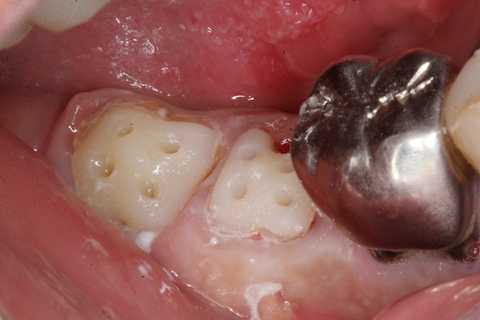

今日も野戦病院シリーズ26(CK破折) 2025.10.25